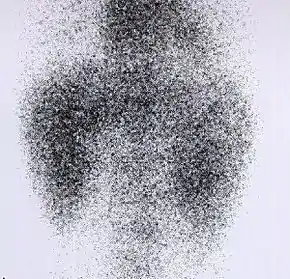

DMSA scan

|  Decreased Tc99m-DMSA uptake in both kidneys, suggestive of renal failure. | |